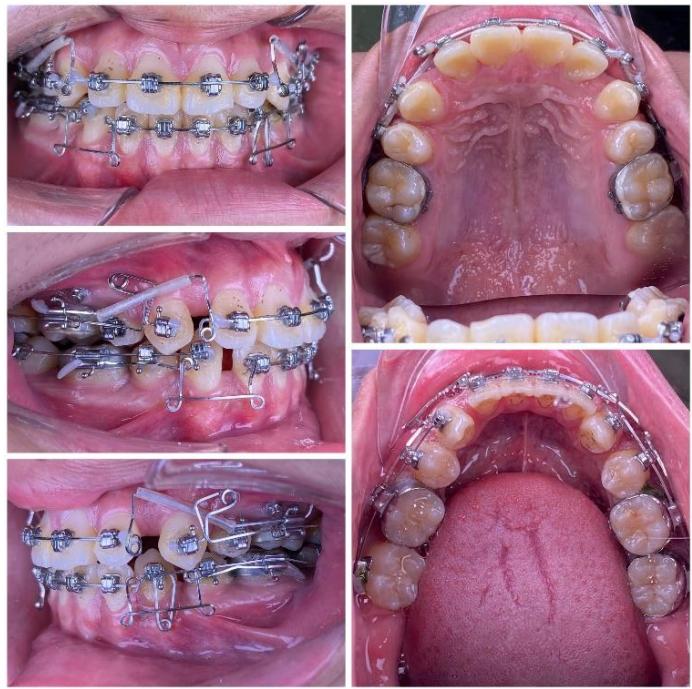

During canine space closure, a commonly observed side effect is an increased tendency for the roots to approach the cortical bone. At the mandibular canine region (tooth 33), due to the close proximity of

the root to the labial cortical plate, tooth movement was slowed when sliding mechanics were applied [10-12]. Under these circumstances, a single-loop was fabricated on a $0.019 \times 0.025$ -inch TMA archwire to generate a root-directing moment, guiding the root into cancellous bone and thereby "reopening" the biological envelope available for tooth movement. The loop was activated at a rate of approximately $1.5 \mathrm{~mm}$ per month to complete the remaining space closure [19-21].

Following completion of canine space closure, a tendency for maxillary canine extrusion was observed. Therefore, two L-shaped loops with elastomeric elements were applied to deliver an intrusive force, reduce extrusion, and re-establish occlusal plane balance.

Figure 8: Space closure performed by segmented loop mechanics for canine retraction, followed by anterior space closure using a retraction arch with three-dimensional torque control

### c) Incisor Retraction using Segmented Mechanics

After completion of canine retraction, the incisor segment was retracted using segmented mechanics according to the Ricketts Bioprogressive philosophy. Retraction arches in both arches were designed to achieve three objectives simultaneously: (i) controlled incisor retraction; (ii) activation of an intrusive component of approximately 2-3 mm to counteract anterior tooth extrusion, which is particularly critical in high-angle patients; and (iii) generation of strong and stable positive torque to achieve three-dimensional control of incisor root movement, especially in the mandibular arch [19-21]. The retraction arches were activated at a rate of approximately 1.5 mm per month while maintaining torque and vertical control.

During the finishing phase, the ART torque spring was continuously maintained in the mandibular incisor region to reduce secondary negative torque and to assist in directing the incisor roots into cancellous bone, thereby protecting the labial cortical plate during the stage when retraction forces generate the most unfavorable moments [22-24].

After the occlusal objectives were achieved, the patient was progressed through finishing archwires (0.016 NiTi; 0.016×0.022 NiTi; 0.017×0.025 NiTi; and 0.017×0.025 stainless steel), in combination with intermaxillary elastics (3/16-inch, 3.5 oz) for midline correction and occlusal settling. Subsequently, space reopening was observed between the maxillary lateral incisors (tooth 2) and canines (tooth 3) bilaterally. A space-closing archwire with L-shaped loops positioned between teeth 2 and 3 was fabricated, and space closure was activated at approximately 1.5 mm per month over a two-month period, resulting in complete space closure. Thereafter, both arches were placed on 0.017×0.025 stainless steel archwires with full-arch elastomeric chains. Intermaxillary elastics were continued to assist in midline correction and to achieve optimal intercuspation.

Figure 9: Re-leveling and alignment phase following anterior space closure of the four incisors